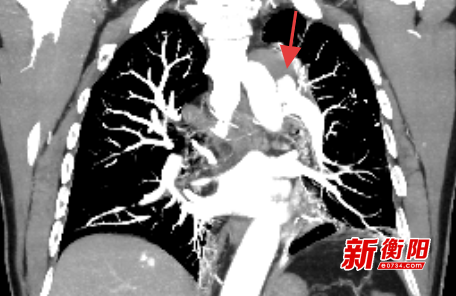

患者袁某,59岁,因“胸背部疼痛约1周”入院,主动脉CTA显示降主动脉夹层并壁内血肿形成,病情极其凶险,如不及时治疗,随时可能因血管破裂导致大出血,危及生命。考虑传统开放手术创伤大、并发症多,医师团队最终决定采用腔内介入治疗方案。

次日,手术团队在DSA(数字减影血管造影)引导下,经股动脉导入导丝导管系统,精确定位夹层破口后,释放量身定制的覆膜支架,成功隔绝血流冲击假腔。术中避开重要分支血管,全程出血不足50ml,患者术后6小时即恢复自主饮食。患者术后转入血管外科病房,48小时内即下床活动,复查显示支架位置良好,假腔内血栓形成,达到解剖学治愈。